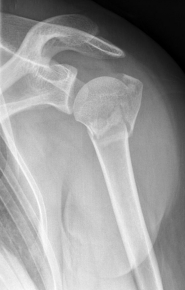

Picture: In the above pictures, a slightly shifted subcapital humeral fracture was internally splinted using intramedullary nail. The left picture is a follow-up examination half a year after the accident and shows the complete healing of the fracture with correct position of the bone.